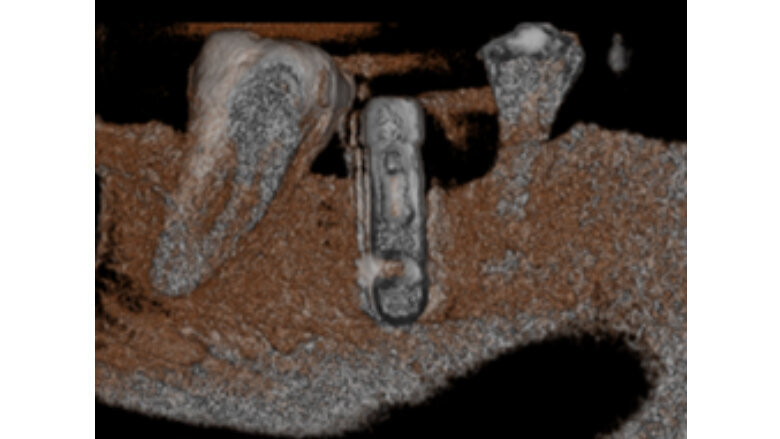

En las imágenes tomográficas (Figuras 2,3) se observa una zona hipodensa en la parte distal del implante, que tiene un halo alrededor del mismo. A los 15 meses, esta imagen hipodensa había desaparecido (Figuras 4,5,6).

Fig 4. Tomografía a los 9 meses. El halo hipodenso en la parte distal del implante ya no existe, ni en la parte inferior, así como tampoco en la parte del reborde óseo; se sigue realizando terapia de fotobioestimulación en la zona.

Fig 6. Imagen de reconstrucción del volumen, donde se puede observar falta de densidad ósea en distal y mesial del implante (inicial).